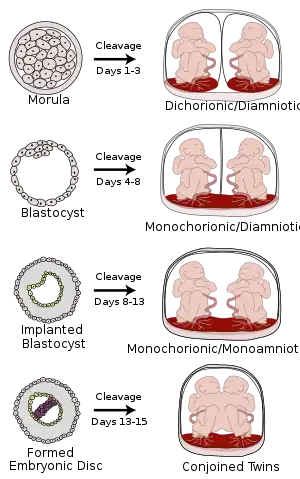

Monochorionic twins are monozygotic (identical) twins that share the same placenta. If the placenta is shared by more than two twins (see multiple birth), these are monochorionic multiples. Monochorionic twins occur in 0.3% of all pregnancies.[1] Seventy-five percent of monozygotic twin pregnancies are monochorionic; the remaining 25% are dichorionic diamniotic.[2] If the placenta divides, this takes place before the third day after fertilization.[2]

Monochorionic twins generally have two amniotic sacs (called Monochorionic-Diamniotic "MoDi"), but sometimes, in the case of monoamniotic twins (Monochorionic-Monoamniotic "MoMo"), they also share the same amniotic sac. Monoamniotic twins occur when the split takes place after the ninth day after fertilization.[2] Monoamniotic twins are always monozygotic (identical twins).[3] Monochorionic-Diamniotic twins are almost always monozygotic, with a few exceptions where the blastocysts have fused.[2]